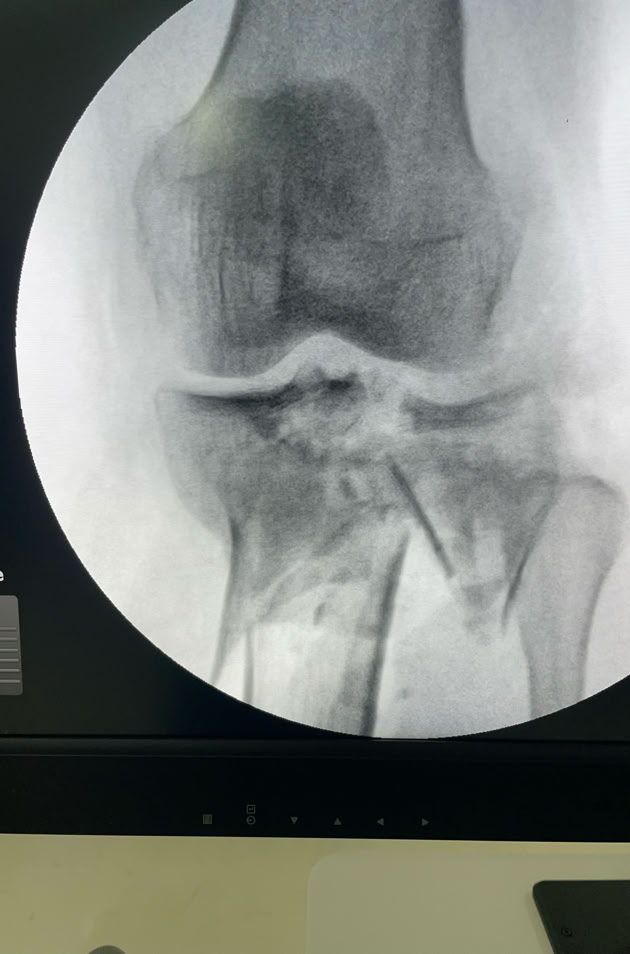

Recibimos la visita de un traumatologo que trabaja en un hospital de Duala y que se desplazó hasta Dschang para que le tratáramos nosotros las lesiones que sufrió al caerse por unas escaleras, “no se fiaba de sus compañeros de hospital”. Una fractura de la extremidad distal del radio que solucionamos con una reducción y estabilización con agujas K (no tenemos placas volares) con excelente resultado  y una fractura diafisaria de humero que solucionamos con unos clavos elásticos (no tenemos clavos de humero). El paciente estaba muy satisfecho a pesar de la parálisis radial que se produjo al fracturarse.